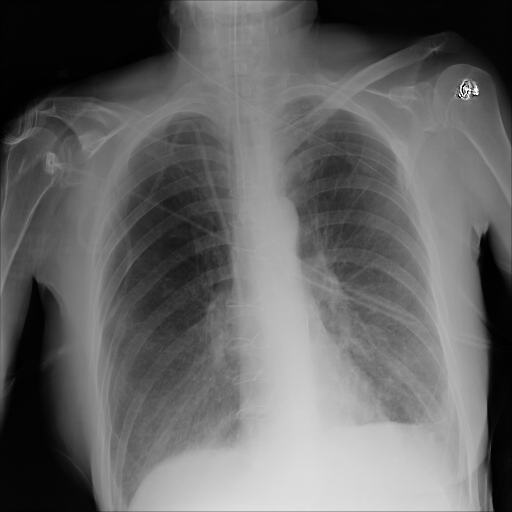

In Fig. 1, we show four ϵitalic-ϵ\epsilon-LDP-processed CXR images of clinical cases obtained with the image domain LDP, which directly imposes the Laplace mechanism on the input image, with different privacy budgets together with the original images. Fig. 2 shows four ϵitalic-ϵ\epsilon-LDP-processed CXR images of clinical cases obtained with DP-GLOW and different privacy budgets together with the original images. In case 1 for DP-GLOW, there is decreased permeability in the bilateral hilar regions. Although this hilar opacity tends to be preserved with a larger privacy budget, the entire image is degraded when the privacy budget becomes 101HWsuperscript101𝐻𝑊10^{1}\cdot H\cdot W. A similar tendency is observed in the images of all the four cases for DP-GLOW; for example, in case 4 with ϵ=101HWitalic-ϵsuperscript101𝐻𝑊\epsilon=10^{1}\cdot H\cdot W, the lung opacity suggesting pneumonia in the right lower lung field is well preserved, while the entire image is degraded.

For DP-GLOW, the AUCs for pneumonia detection significantly change from 0.539 to 0.807, while the privacy budget varies from 101HW(=2,621,440)10^{1}\cdot H\cdot W(=2,621,440) to \infty. This means that this range of the privacy budget is indeed meaningful whereas the privacy budget is very large compared with usual values of ϵitalic-ϵ\epsilon-LDP for scalar quantities. This finding implies that we must normalize the privacy budget so that we can consistently handle ϵitalic-ϵ\epsilon-LDP for vector quantities. To normalize the budget, we compute the privacy budgets per image pixel. To this end, we intentionally indicated the privacy budget to have a common factor HW𝐻𝑊H\cdot W. Therefore, the actual privacy budgets per image pixel in this study are from 101superscript10110^{1} to \infty, which are not much larger than commonly accepted privacy budgets.

Most of the approximate forms in CXR images are preserved and privacy is not protected with the image domain LDP. On the other hand, given a low privacy budget, DP-GLOW deforms the image so much that individuals cannot be identified. However, the AUCs for pneumonia detection are similar with the low privacy budget between DP-GLOW and the image domain LDP.